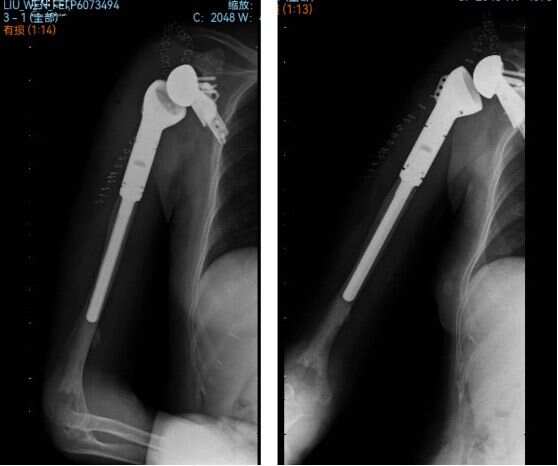

術(shù)后患者狀態(tài)良好,第二天即可在患肢支具保護(hù)下進(jìn)行活動(dòng),并能夠進(jìn)行被動(dòng)的肩關(guān)節(jié)運(yùn)動(dòng)。術(shù)后復(fù)查X片顯示肩關(guān)節(jié)假體位置良好,功能康復(fù)恢復(fù)良好。

本例手術(shù)是武漢協(xié)和骨科醫(yī)院首例采用3D打印截骨導(dǎo)板與個(gè)性化假體,實(shí)現(xiàn)反肩關(guān)節(jié)及半肩胛盂置換的“私人定制”的手術(shù)。此項(xiàng)技術(shù)的成功開(kāi)展,將為更多肩關(guān)節(jié)周圍腫瘤病人帶來(lái)保肢希望,造福廣大患者。